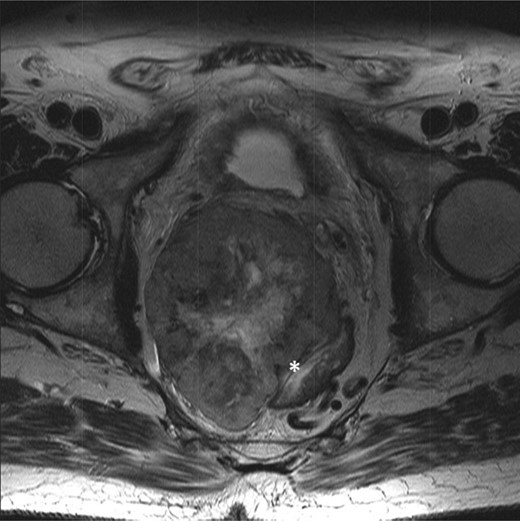

T2-weighted axial showing the same mass lying adjacent to the anterior wall of the rectum (*).

T2-weighted axial images after 3 months of imatinib mesylate therapy. The mass has shown a significant reduction in size (white star).